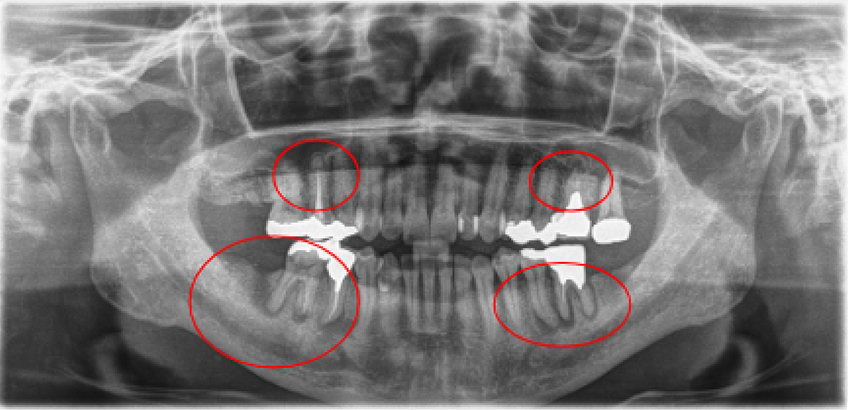

2008年03月 初診時

2008年06月 歯周基本治療終了後

2016年6月 約4年経過

2023年12月 上顎残存歯

最終補綴処置終了後 約2年経過

| 治療内容 | 重度歯周病・インプラント・矯正治療 |

|---|---|

| 患者様の年齢 | 52歳 |

| 患者様の性別 | 男性 |

| 治療期間 | 初診時より4年 |

| 治療回数 | 矯正治療・歯周治療・インプラント治療合わせて130回程度 |

| 治療費用 | インプラント:約450万円/歯周病:15万円 矯正:15万円/補綴治療:110万円 |

| 治療で得られるメリット |

|

| 治療する際に起こる リスク・副作用 |